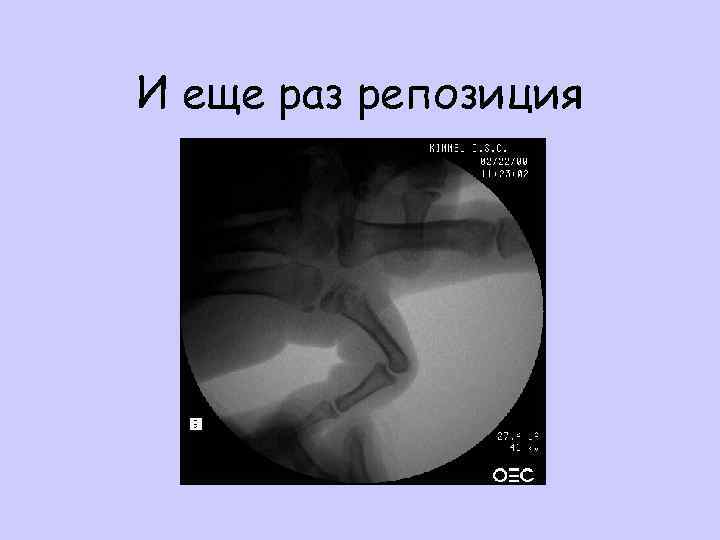

И еще раз репозиция